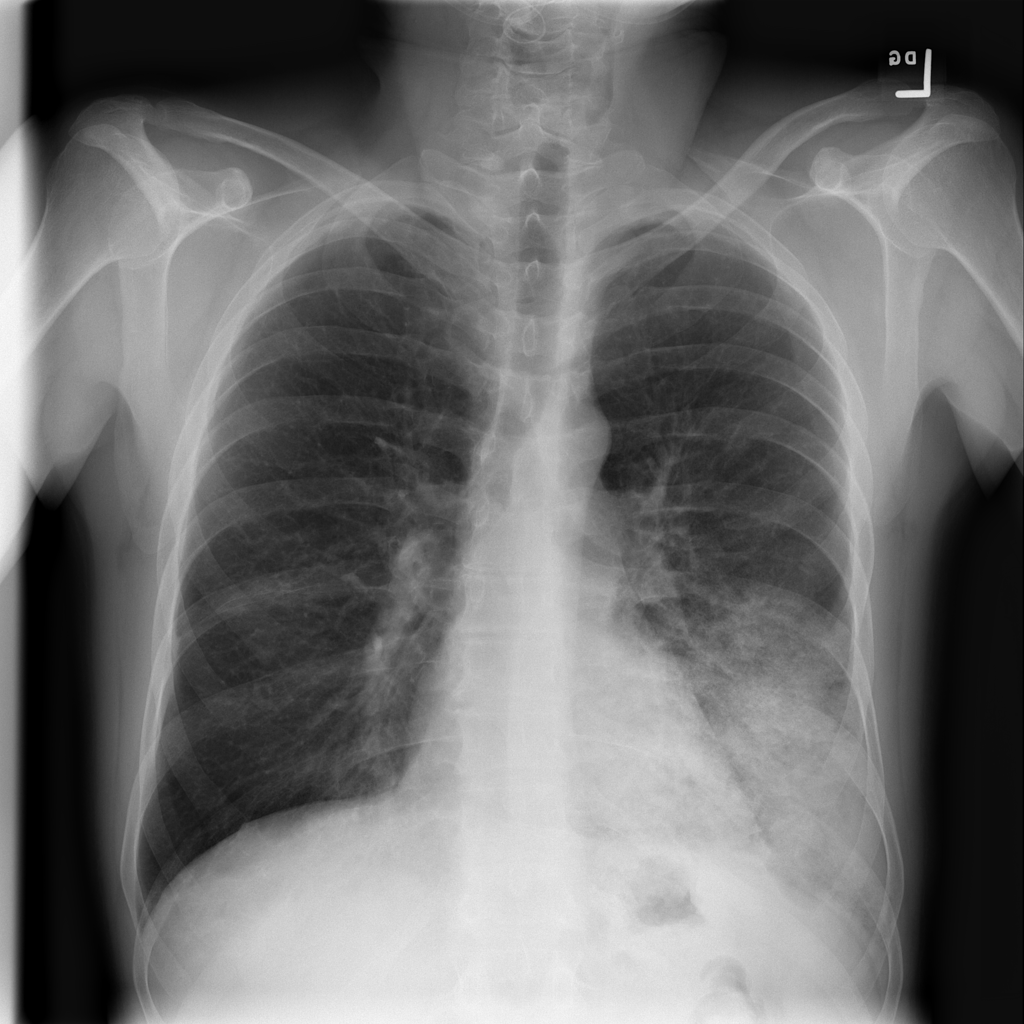

PAT-C0E5 · IMG-015Pneumonia

PAT-C0E5 · IMG-015

AP